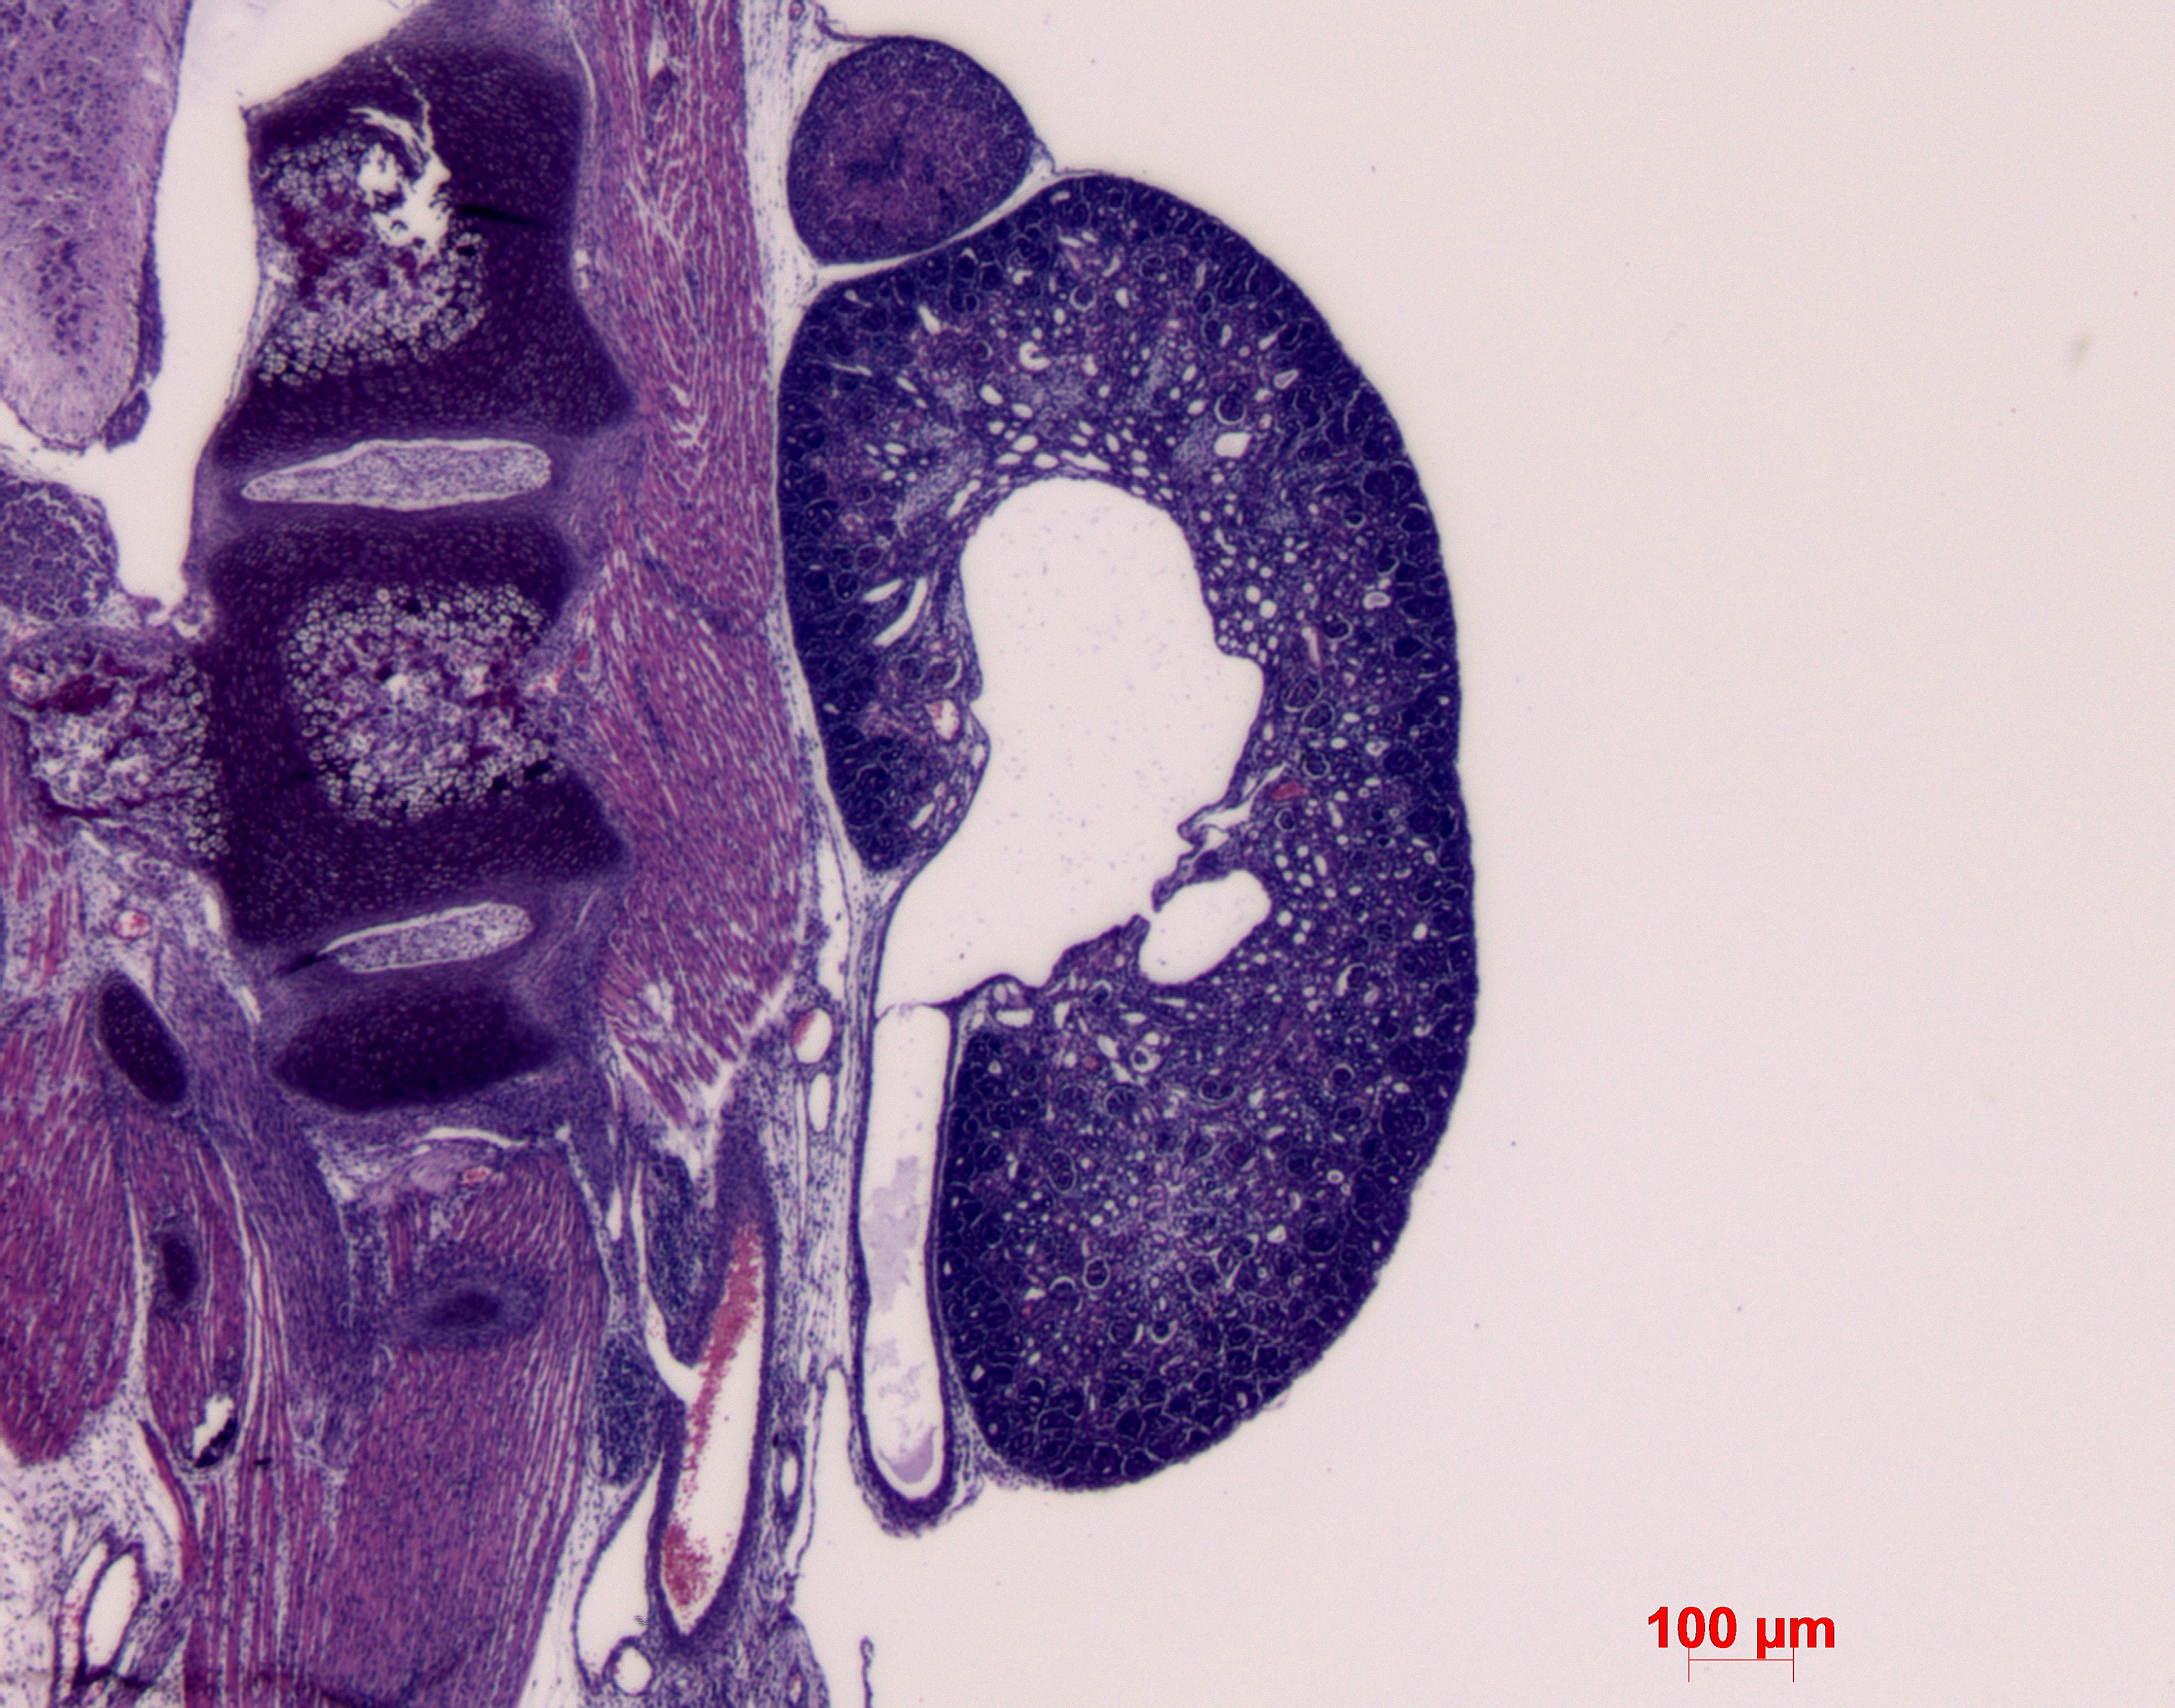

Caption Mutant 1449-007-LA kidneys show hydronephrosis and hydroureter

Nek8b2b1449Clo NIMA (never in mitosis gene a)-related expressed kinase 8; Bench to Bassinet Program (B2B/CVDC), mutation 1449 Cecilia Lo

Nek8b2b1449Clo/Nek8b2b1449Clo C57BL/6J-Nek8b2b1449Clo